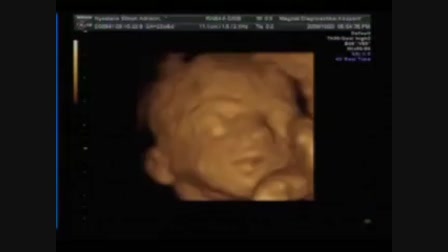

Alsóőrsön nyaralt a család.A strandon készült a videó